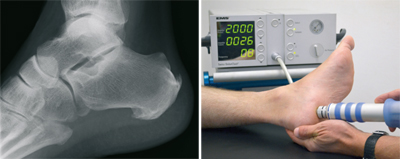

Fersensporn

Der plantare Fersensporn (unten an der Ferse) entsteht durch eine Überlastung der das Fußlängsgewölbe verspannenden Faszie. Bindegewebsschwäche, Fehlbelastung, Fehlstellung, aber auch Übergewicht können hierfür verantwortlich sein. Durch die Überlastung entsteht zwischen dem Fersenbein und der Anhaftungsstelle dieser Faszie eine zunehmende Gewebeschädigung, verbunden mit einer Verknöcherung, dem sogenannten Fersensporn. Nicht der Sporn selbst, sondern diese Gewebeschädigung verursacht die Schmerzen. Sie treten zunächst vorwiegend belastungsabhängig auf, später aber auch in Ruhe. An erster Stelle der möglichen Behandlungen steht die Versorgung mit speziellen orthopädischen Einlagen. Auch Injektionen, direkt an den Fersensporn, haben ihren Stellenwert. Sehr bewährt hat sich die risikofreie Stoßwellentherapie, die auch in unserer Praxis durchgeführt wird. Alternativ kann Röntgenbestrahlung eine Ausheilung bewirken.

Versagen alle nicht operativen Maßnahmen, besteht auch hier eine operative Behandlungsmöglichkeit. Dabei wird über einen kleinen Schnitt am inneren Fersenrand die Faszie eingekerbt, die Spannung lässt nach und die Gewebeschädigung kann ausheilen.